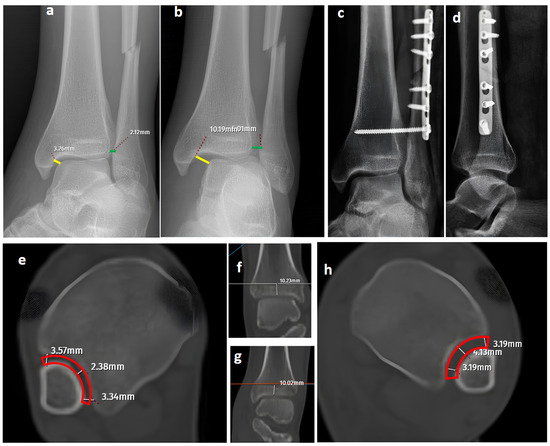

Three different sets of images were prepared and evaluated by three orthopedic surgeons with varying levels of experience during three separate sessions (a senior resident surgeon, a staff orthopedic surgeon, and a senior orthopedic surgeon). The image sets included standard AP/lateral radiographs and mortise radiographs, standard AP/lateral radiographs and GAASA images, and standard AP/lateral radiographs and CT axial (10 mm over the plafond) and coronal images. One week prior to evaluating the image sets, all evaluators were informed in a meeting about the radiological findings indicating syndesmosis injuries, including evaluations of the interosseous clear space, tibiofibular clear space, medial clear space, talo-crural angle, and tibiofibular overlap [1] (Figure 1, Figure 2 and Figure 3).

Figure 1.

A trimalleolar right ankle fracture. (a,b) Standard AP and lateral views showing a bimalleolar fracture with a normal distal tibiofibular overlap (green line). (c) A mortise view showing an open distal tibiofibular distance (red arrow) indicating syndesmosis injury. (d) A GAASA view showing lateral displacement of the talus with a shift in the medial malleolus and distal fragment of the fibular segment. However, the proximal segment of the fibula is in place, indicating that the proximal syndesmosis is intact (yellow arrow). Axial CT images of the injured right ankle (e) and the uninjured left ankle (f) show measurement of the tibiofibular space (red block bow), which appears similar and within normal ranges, indicating an intact syndesmosis.

In our series, 19 of 36 SER type II and IV cases did not involve syndesmotic injury (Figure 1), which is consistent with the idea that medial and lateral injuries must be carefully assessed before surgical stabilization. These findings highlight that GAASA imaging is particularly reliable in PER injuries, where all medial and lateral structures are disrupted and the fibula is extensively fractured. In such cases, gravitational force causes the talus to exert downward pressure on the distal fibular fragment, producing clear widening of the medial clear space and distal tibiofibular joint [28]. Maisonneuve injuries, not classified by the Lauge-Hansen system, are inherently unstable and require surgical syndesmosis stabilization [29]. In our study, three cases had clear distal tibiofibular widening without pathological medial clear space widening (Figure 2). This contrasts with the cadaveric study by Krahnebühl et al., which reported that stress radiographs are reliable only when deltoid and syndesmotic injuries coexist, but are ineffective for isolated syndesmosis injuries [5]. Our findings suggest that even when the medial malleolus and deltoid ligament remain intact, gravitational force alone can cause lateral fibular displacement, resulting in decreased tibiofibular overlap.